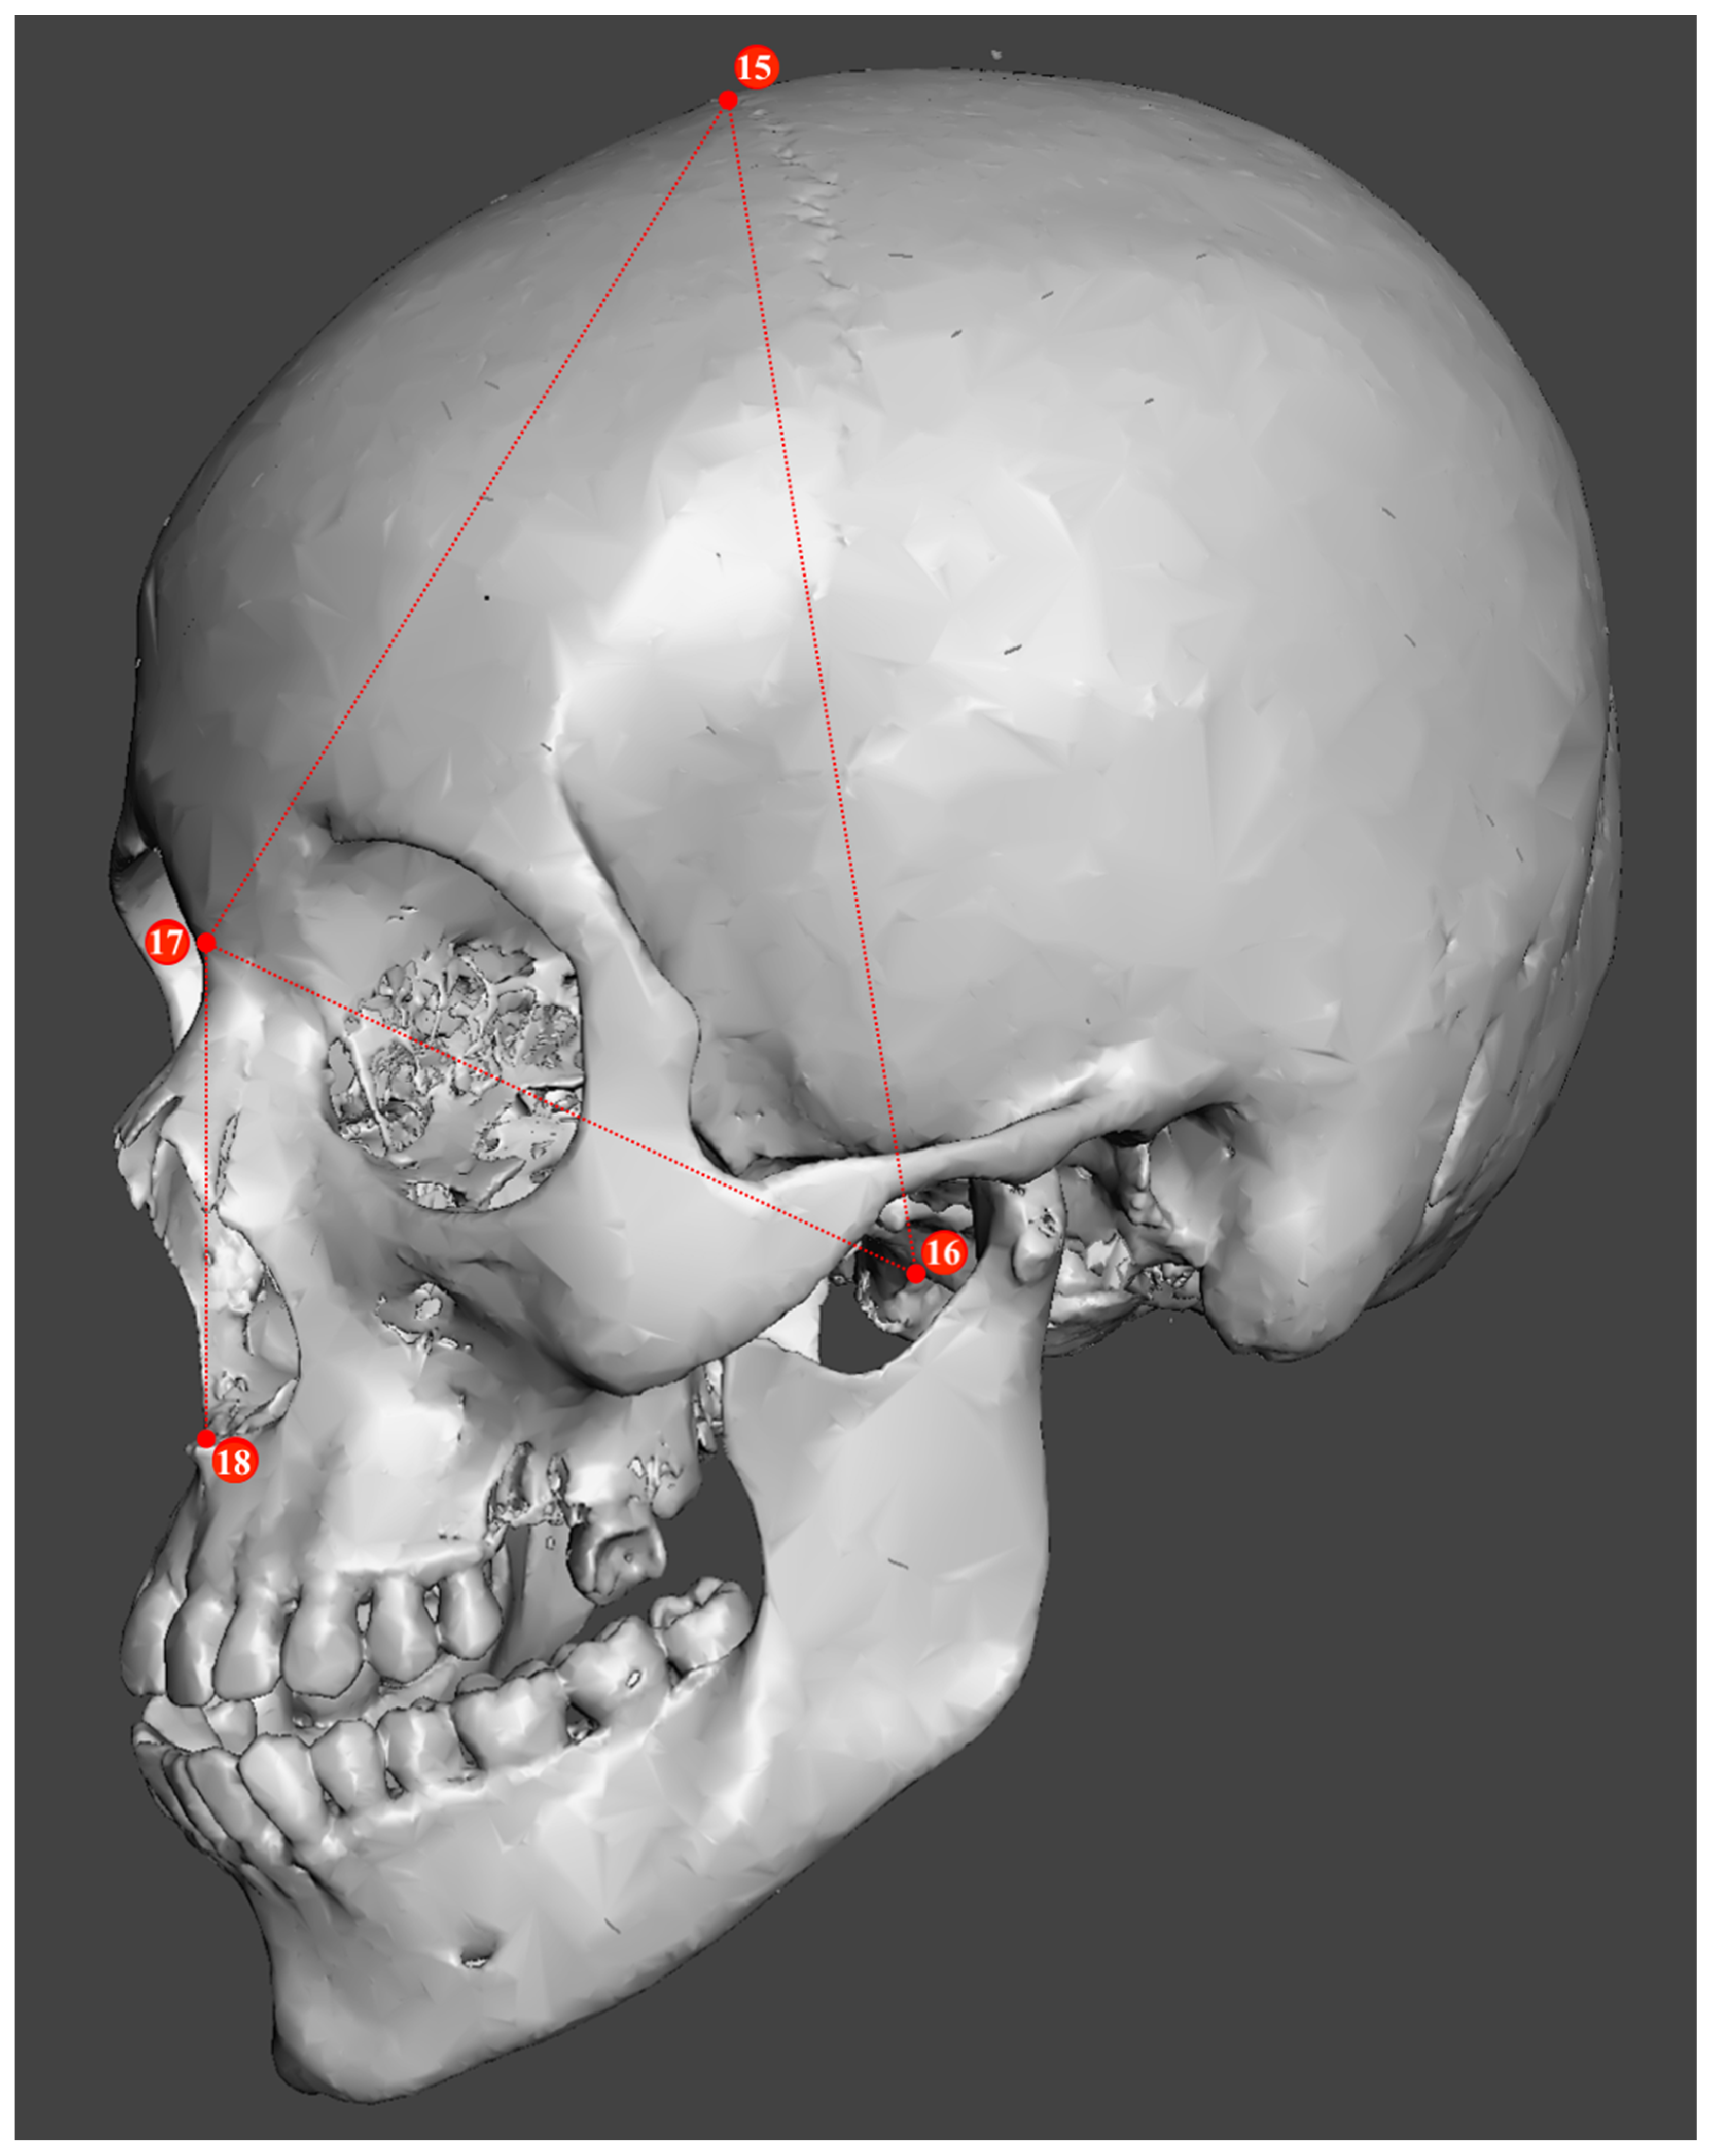

2.2. Study Sample Preparation and Data Collection

| Metric Measurements | |

|---|---|

| 1. Minimum frontal breadth (ft-ft) | 10. Bicondylar breadth (cdl-cdl) |

| 2. Orbital height | 11. Biauricular breadth (au-au) |

| 3. Upper facial height (n-pr) | 12. Foramen magnum breadth |

| 4. Parietal chord (b-l) | 13. Occipital chord (l-o) |

| 5. Glabella occipital length (g-op) | 14. Bigonial breadth (go-go) |

| 6. Mastoid length | 15. Basion–bregma height (ba-b) |

| 7. Mandibular length | 16. Basion–nasion length (ba-n) |

| 8. Maximum ramus height | 17. Frontal chord (n-b) |

| 9. Bizygomatic breadth (zy-zy) | 18. Nasal height (n-ns) |